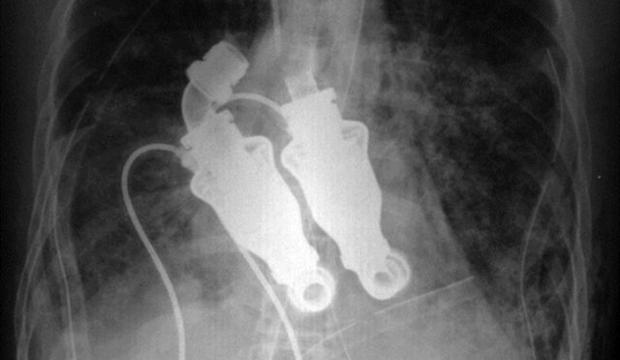

55 настай Крейг Льюис өнгөрсөн оны гуравдугаар сард зүрхний дутагдлаас болон сандарч эмч нар яаж ч тусалж чадалгүй нас барсан байна. Гэвч “Техасын зүрхний мэс заслын хүрээлэн”-гийн хоёр эмч үүнийг шийдэх арга сэдэж зүрхний үйл ажиллагааг орлон цусыг биед нь байнаг шахан түгээж байх төхөөрөмж суулгахаар шийдвэрлэсэн байна. Доктор Билли Кон, Бад Фрезер нар Крейгийн зүрхний оронд өнөөх төхөөрөмжөө суулгажээ. Мэс заслаас хойш нэг хоног болоод өвчтөн ухаан орж, бие нь ямар ч зовуиргүйи сайн байгаа талаар эмч нартаа хэлсэн байна. Эмч нар энэ төхөөрөмжөө хүний биед суулгахын өмнө тугалд 50 гаруй удаа суулгаж туршсан юм байна. Мал суурилуулсны дараа нэг хоноод л зүгээр идэж, унтаж, хэвийн байдлаар хөдөлж байсан байна. Харин венийн судсаар цус яг зүрхний хэмнэлээр гүйхгүй байх дутагдал хааяа гарч байжээ.

Льюс Крейгийн өвчин маш богино хугацаанд даамжирч бүр 2011 оны гуравдугаар сард эмчлэгч эмч нь үзээд гайхамшиг л тохиодоггүй юм бол 12 цагийн дараа нас барна гэж хэлж байжээ. Ийм ч болохоор түүний гэргий Линда дээрх хоёр эмчид ямар ч байсан түүний цээжинд энэ зүрх орлуулагчаа суулгахыг зөвшөөрчээ. Энэ нь тэгээд ихэнхийг нь гэрийн нөхцөлд бэлтгэж угсарсан бүтээл юм байна. Одоо Крейгийн “зүрх орлуулагч” зогсолтгүй ажиллаж цусаа шахсаар байгаа гэнэ.

“Би түүний цээжинд чихээ наагаад чагнахаар зүрхний цохилт биш, зүгээр л шийгах шиг чимээ сонсогддог юм, сонин шүү” хэмээн анхны зүрхгүй хүний гэргий Линда хэлж байна. Харин Крейг бол манай гариг дээрх зүрхгүй цор ганц хүн болохоор түүнд зүрхний цохилт гэж байхгүй даралтыг нь хэмжих аргагүй юм.